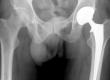

Hip Pain

Do I need a new hip

Do I need a hip replacement